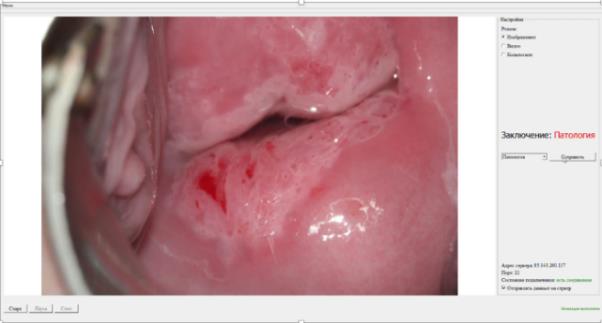

Разработано медицинское изделие «Программа ЭВМ на основе искусственного интеллекта для повышения точности диагностики рака шейки матки». Выполнена валидация конечного программного продукта (Нейросетевой алгоритм), созданного для ранней диагностики рака шейки матки в клинических условиях. Проведен сбор параметров о чувствительности (81%) и специфичности (86%), площадь под кривой (89%) метода, отладка, повторные повторяющиеся тренировки нейронной сети с учетом ранее распознанных ошибочных распознаваний. С целью регистрации разработанной программы ЭВМ как медицинского изделия, успешно пройдены технические и клинические испытания.